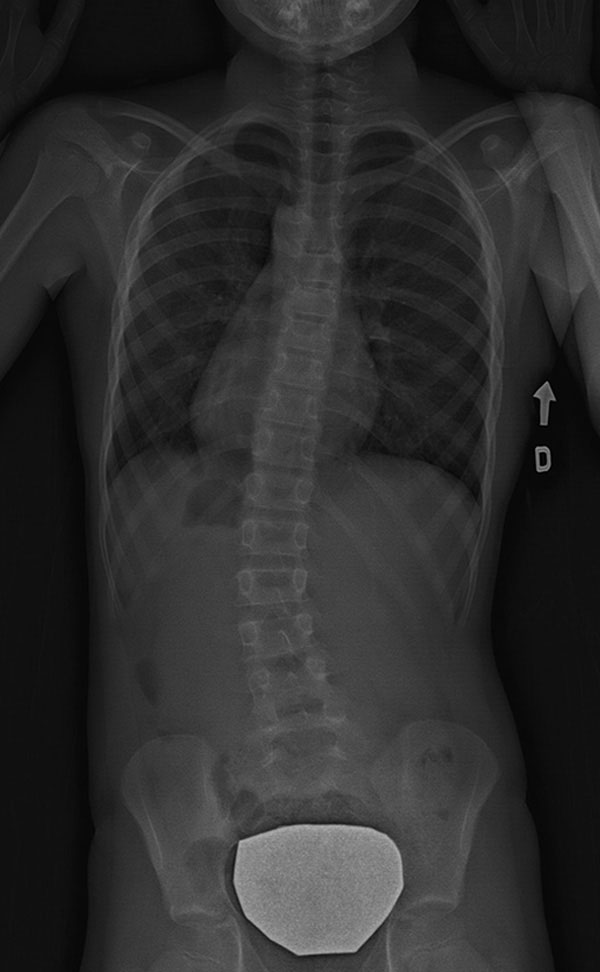

Scoliose thoraco-lombaire (dorso-lombaire) – située dans la colonne vertébrale entre la région thoracique et le bas du dos.

![]() |